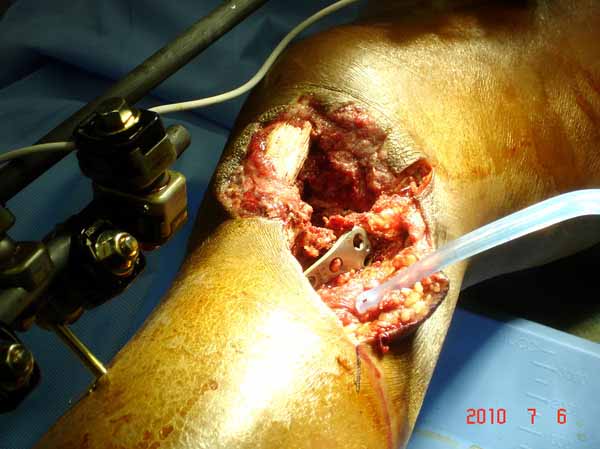

Из всех перечисленных методов подходит вариант пластики аутокостью и усиление (арматура) шурупами. Основная задача сохранить интактную медиальную стенку и латеральный кортекс. Доступ передне-латеральный, но надо работать спереди шейки через небольшое окно в 10-15 мм. Фиксацию надо проводить между медиальной тонкой стенкой головки и латеральным кортексом. Каннюлированные шурупы 6.5 мм очень грубые и могут разрушить остаток стенки. Фиксировать надо кортикальными шурупами 3.5 мм, которые создадут мостик и арматуру в шейке. Провести по периметру шейки 4, и в центре пару шурупов. Во время операции и при манипуляции соблюдать осторожность, в любой момент может наступить стресс перелом. Заранее надо заказывать длинные шурупы!